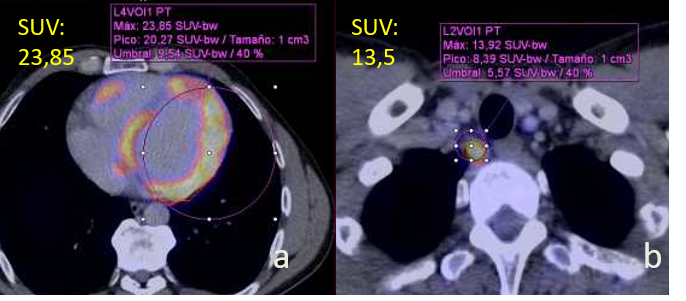

FDG PET/CT with a patchy tracer uptake in the LV & RV (a) and in a paratracheal lymph node (b)..png)